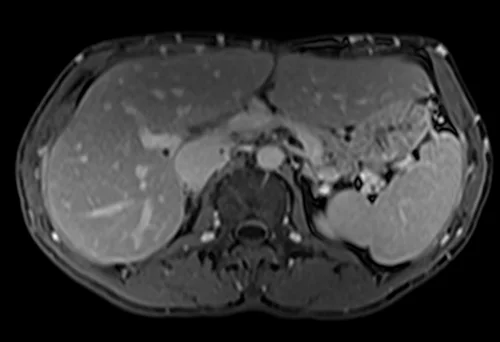

MRV abdomen axial t1 flash post contrast image 4 - MRI